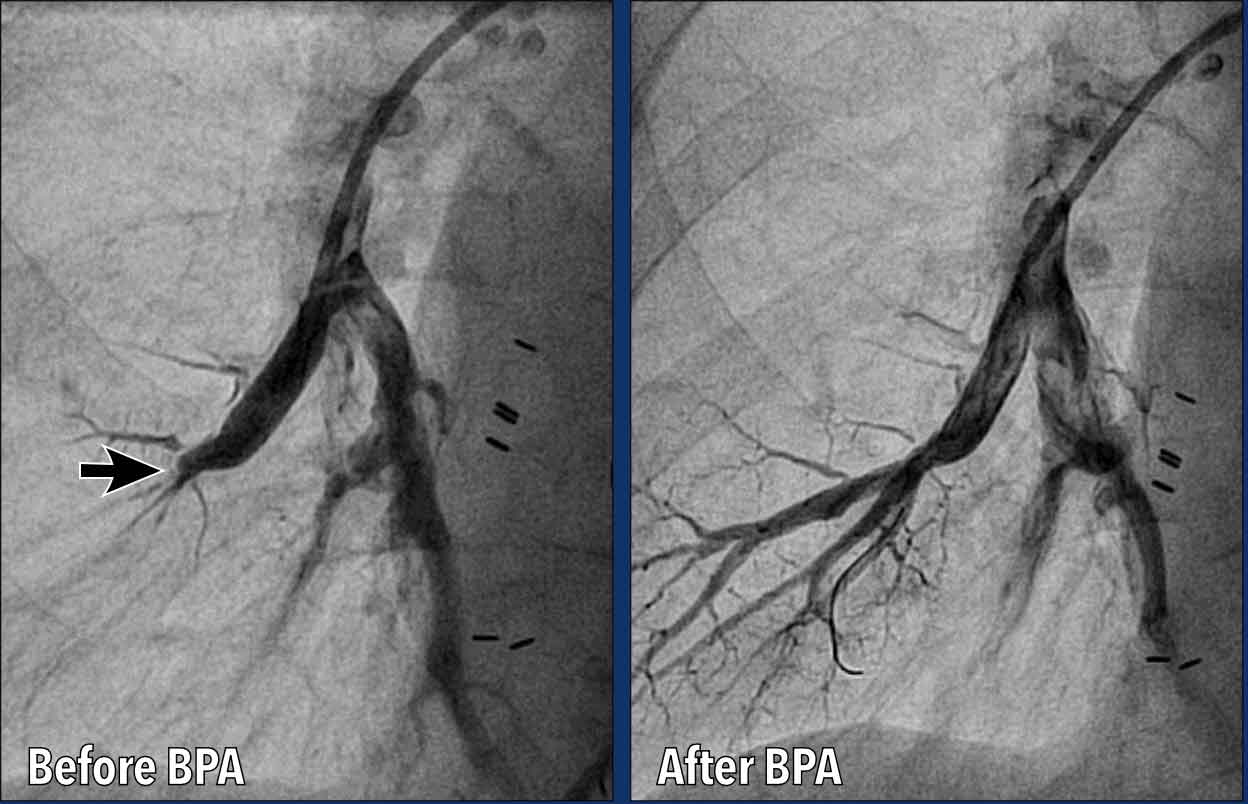

Balloon Pulmonary Angioplasty (BPA)

Balloon Pulmonary Angioplasty (BPA)  is a catheter-based interventional procedure used to treat  CTEPH.

BPA is a minimally invasive alternative to surgery for patients with:

• Inoperable CTEPH (e.g., distal disease not accessible by surgery).

• High surgical risk.

• Residual pulmonary hypertension after pulmonary endarterectomy (PEA).

Images

Before BPA there is acute tapering and occlusion of a basal segmental pulmonary artery of the right lower lobe.

After BPA the artery is patent, with restored flow into the segmental arteries.